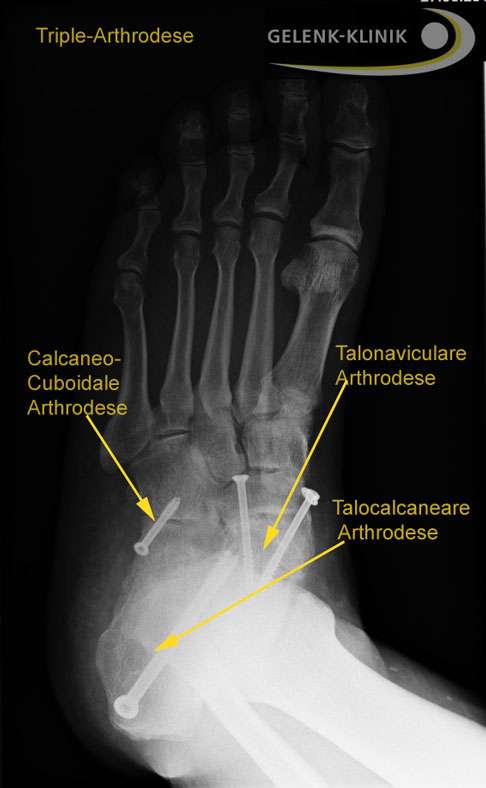

Bei einer Triple-Arthrodese werden alle drei Anteile des unteren Sprunggelenks versteift, also alle Fußgelenke, die mit dem Sprungbein verbunden sind. Dazu zählen das zwischen dem Sprungbein und dem Fersenbein liegende talocalcaneare Gelenk (TCG oder Subtalargelenk) und die beiden vor dem Sprungbein liegenden Gelenke: das Sprungbein-Kahnbein-Gelenk (talonaviculares Gelenk, TNG) und das Fersenbein-Würfelbein-Gelenk (calcaneocuboidales Gelenk, CCG), welche gemeinsam das sog. Chopart-Gelenk bilden.

Für die Triple-Arthrodese entfernt der Fußchirurg zunächst den Knorpel in den betroffenen Gelenken: im Sprungbein-Fersenbein-Gelenk, im Sprungbein-Kahnbein-Gelenk und im Fersenbein-Würfelbein-Gelenk an der Fußwurzel.

Als nächstes werden die Knochenflächen vorbereitet, damit sie optimal zusammenpassen. In einigen Fällen ist es notwendig, Teile des Knochens zu entfernen oder zu glätten. Dann fixiert der Operateur die Knochen in der gewünschten Position. Dies kann mithilfe von Schrauben, Platten, Nägeln oder Drähten erfolgen, die die Knochen stabil aneinander halten.